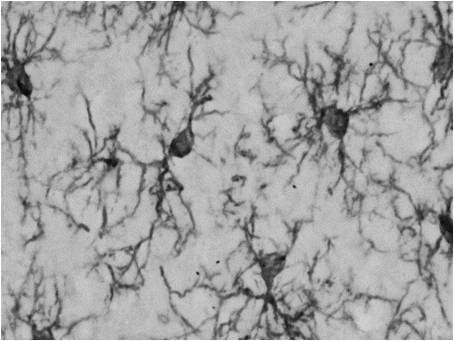

→使用抗Iba1,单克隆抗体(Wako目录号012-26723)小胶质细胞的定位信号清晰,与抗Iba1,兔多克隆抗体的效果相同(Wako目录号019-19741 019-19741)。

●样品:7周龄大鼠,7周龄小鼠或成年的大脑皮质

●切片:50μm冰冻切片(小鼠和大鼠),40μm冰冻切片(狨猴)

●染色法:ABC法+ DAB染色

●抗体浓度= 1:500